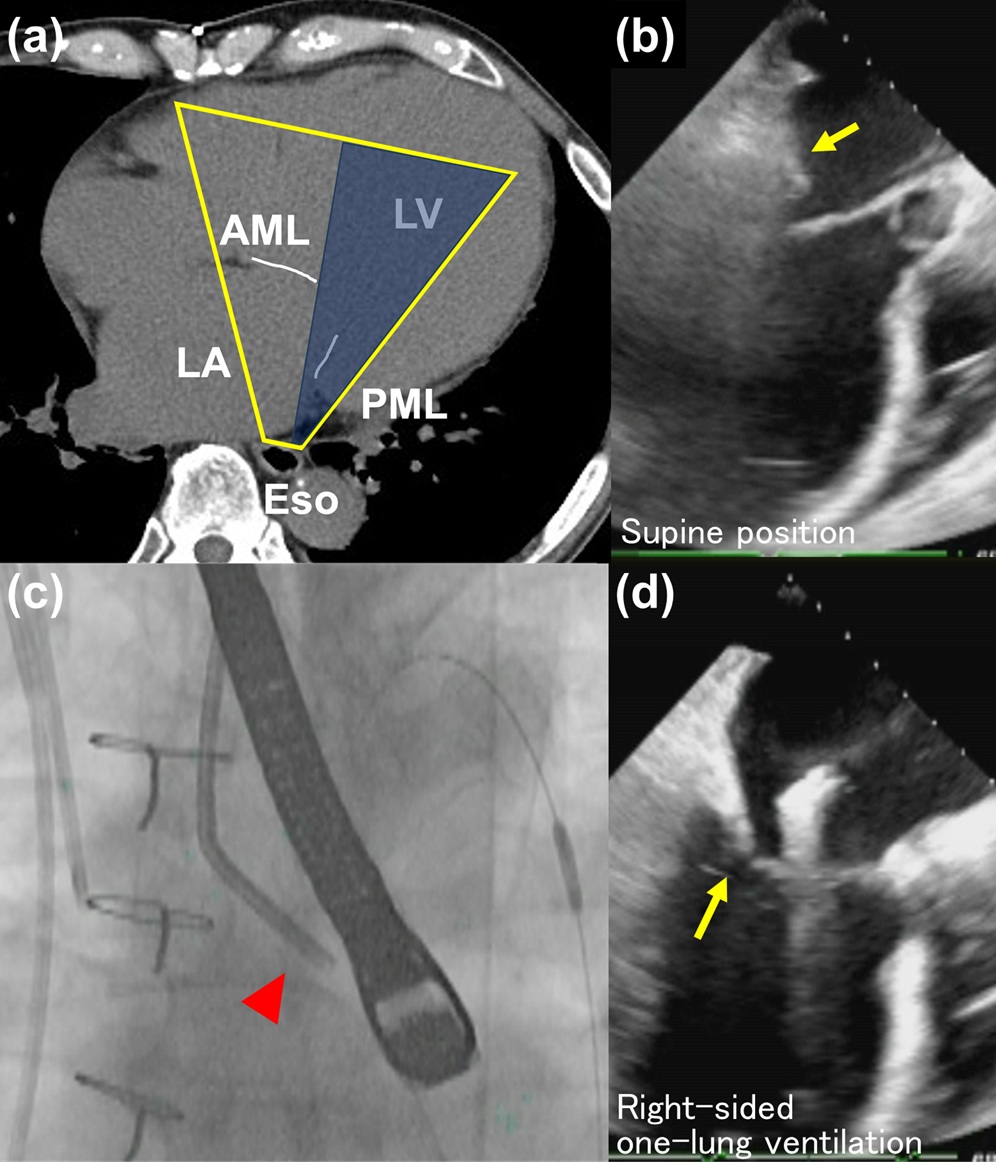

Enhancement of posterior mitral leaflet imaging quality during the MitraClip procedure using one-lung ventilation.

MitraClip手技における片肺換気により僧帽弁後尖が明瞭に描出できた一例

MitraClip手技において、術中経食道心エコーは重要な役割を担っており、特に僧帽弁の描出は手術の成否に大きな影響を与える。本症例では後尖の描出に極めて困難を伴ったが、左主気管支をブロックした右片肺換気法を用いることにより後尖が明瞭に描出された。確実なクリップ手技が遂行できた。

今後もハートチームが各自の専門性を発揮しながら連携を図り、安全で確実な手技の継続に寄与していきたいと考える。